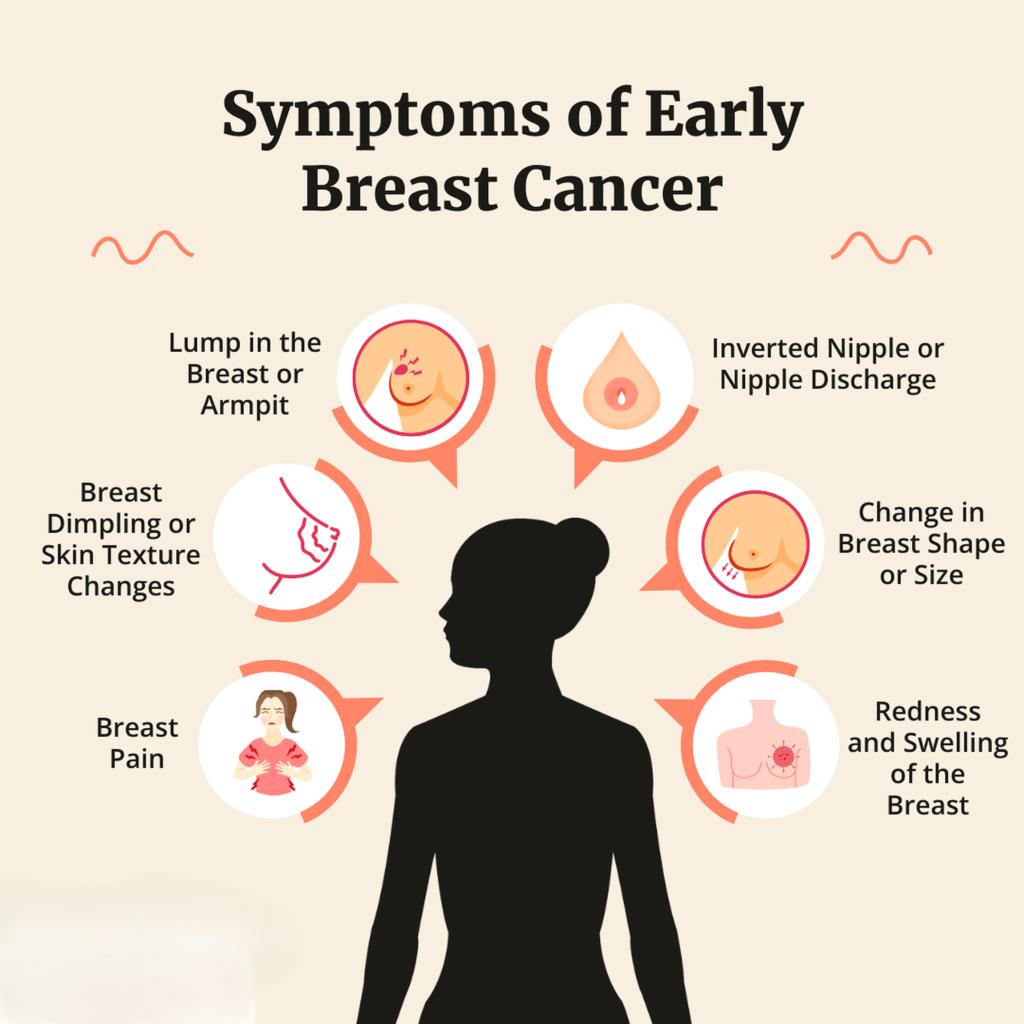

- Lump that does not go away

- Rapidly growing lump

- Lump associated with pain, skin changes, or discharge